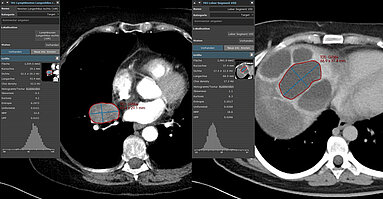

University Hospital Tübingen: Study shows prediction power of clinical and CT imaging biomarkers

A recent retrospective study [1] conducted by researchers at University Hospital Tuebingen focused on identifying imaging and clinical predictors of overall survival and treatment response in…